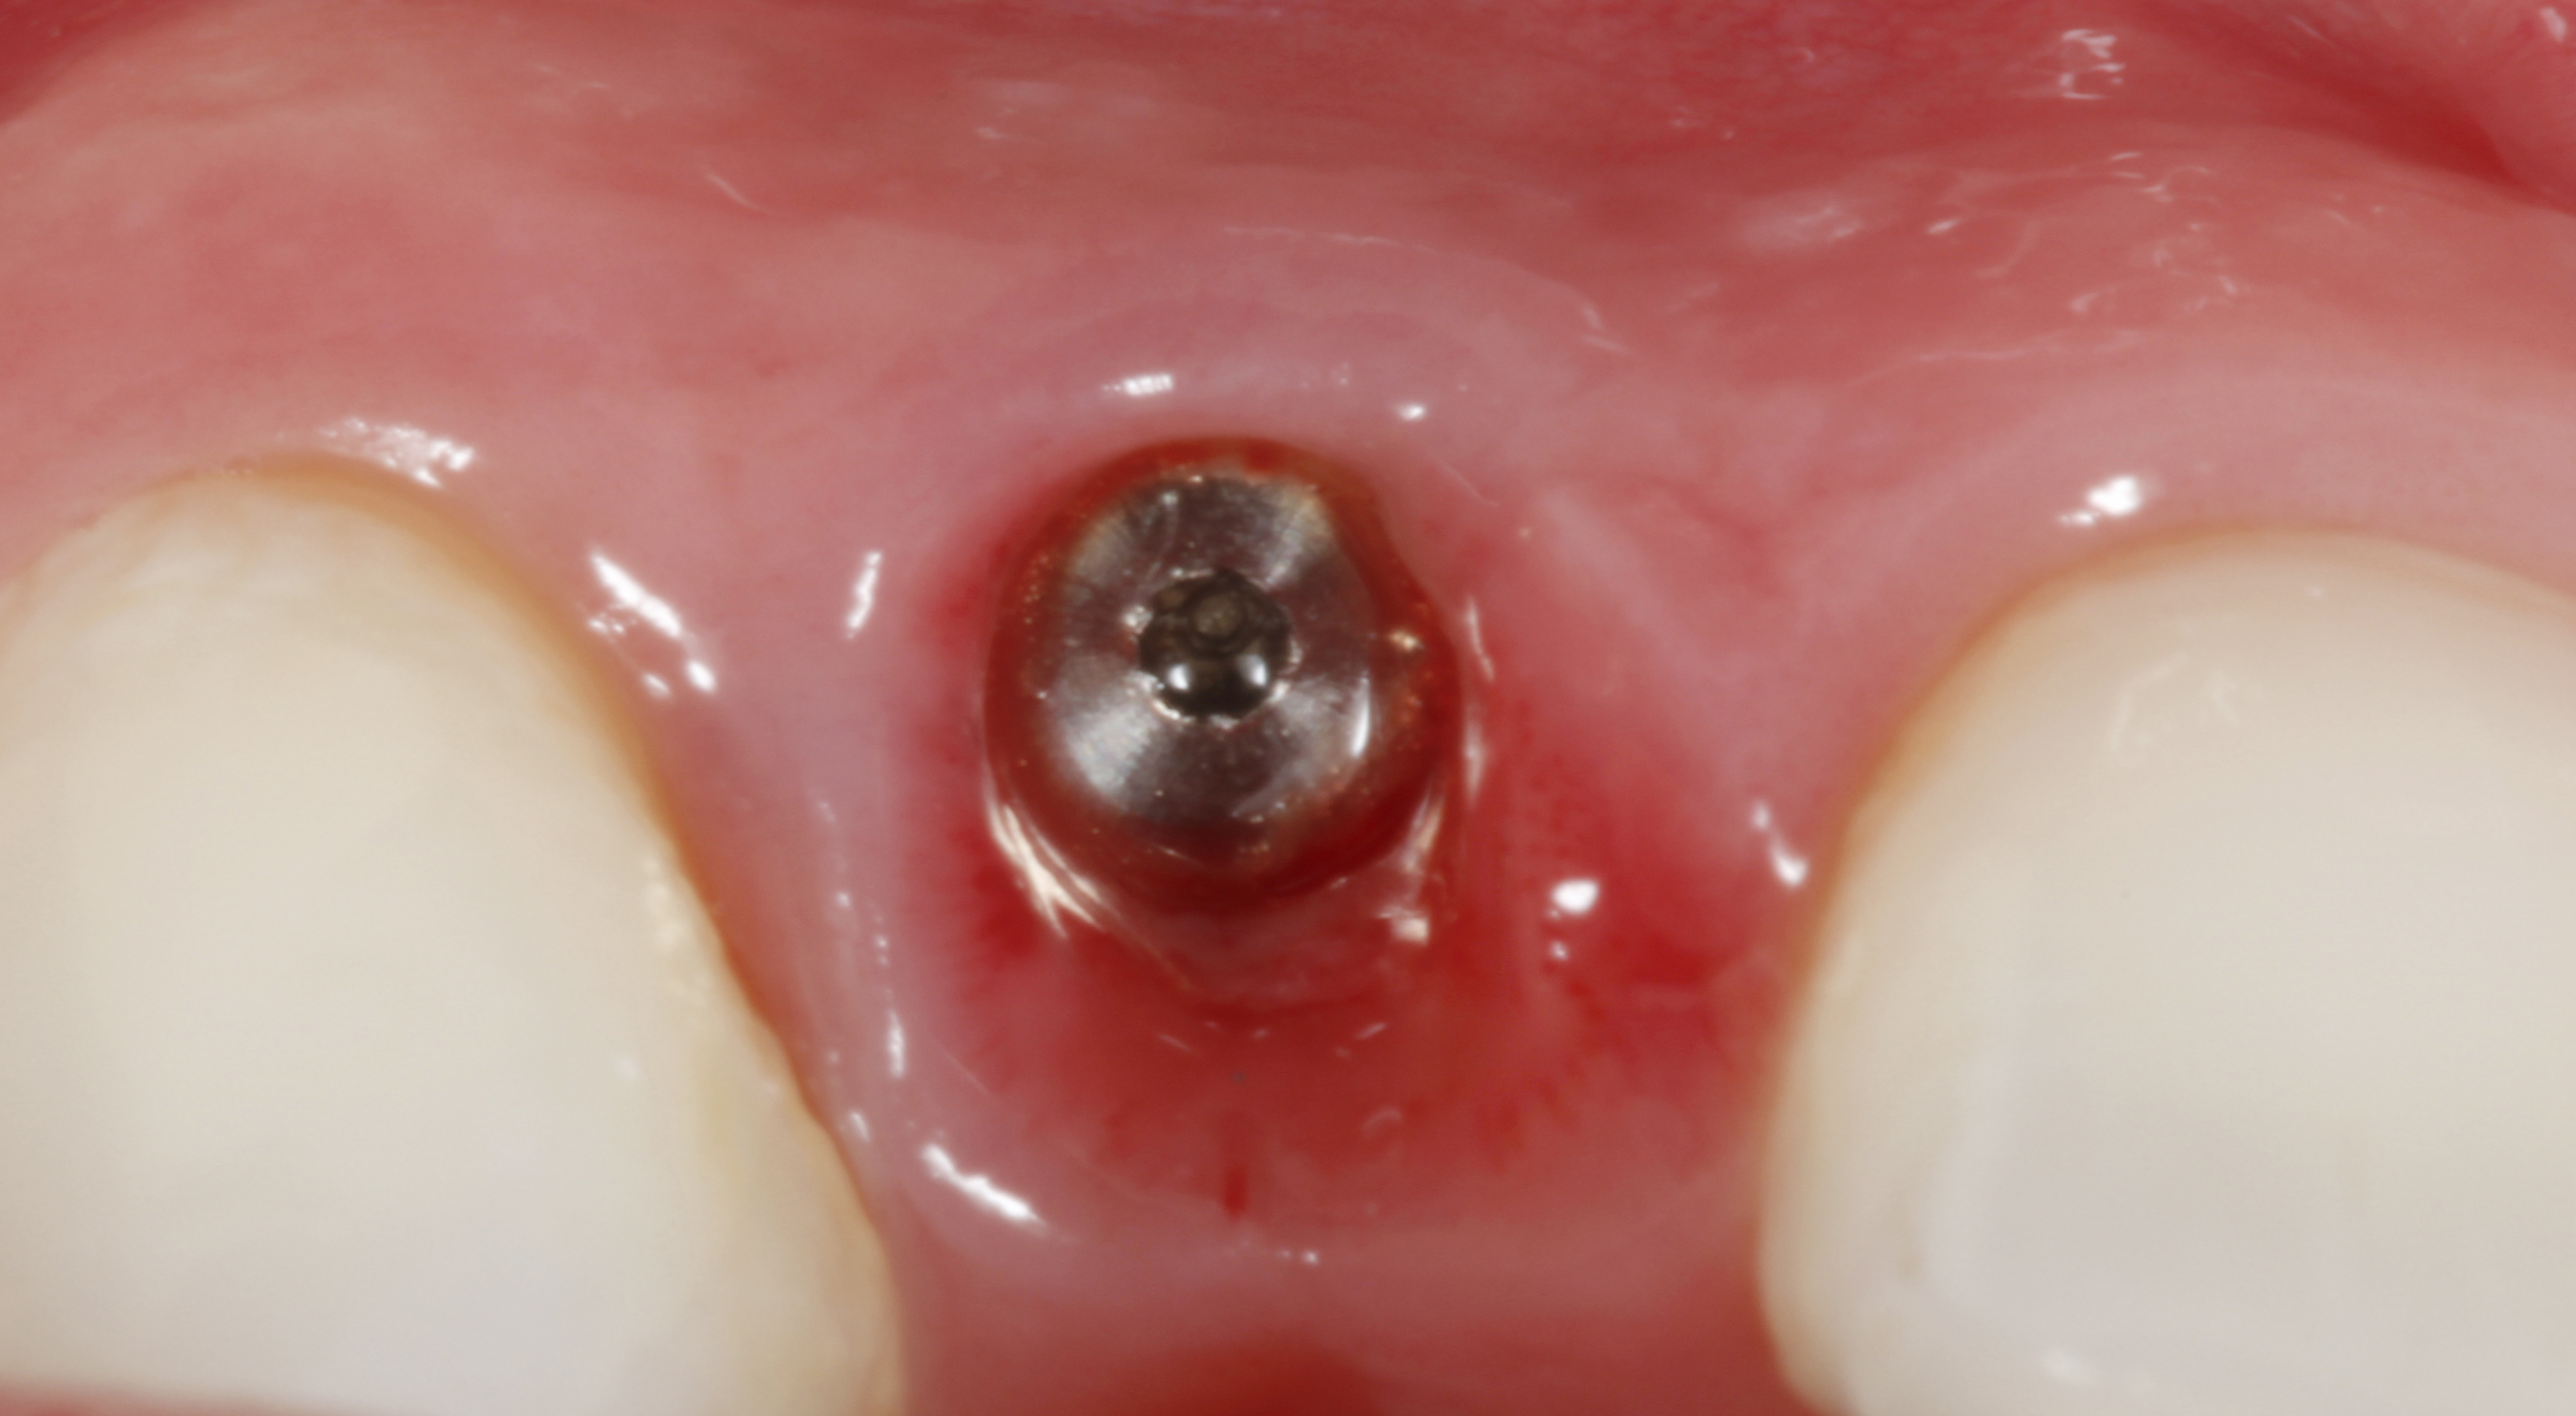

The crown and screw-retained custom abutment were removed, and a surgical cover screw was placed into the implant, thereby allowing spontaneous gingival augmentation in situ (Figure 33 and Figure 34). Note that the lingual aspect of the implant site was significantly more coronal than the labial aspect, which was positive because the defect would be limited to a facial–lingual defect. A fixed RBR bridge was cemented on the adjacent teeth and used as a tooth-supported transitional provisional restoration (Figure 35). A few weeks were allotted to let the soft tissue heal and migrate around the cover screw (Figure 36) to see if there would be complete coverage, thereby allowing a soft-tissue augmentation procedure to be performed with primary flap closure as in clinical scenario No. 2. The major obstacle in achieving a positive tissue response was that the implant depth was also deficient because the implant–abutment connection was at the level of the free gingival margin. It was decided that the best treatment option would be to remove the implant. A high-powered reverse-torque device (Fixture Remover Kit, NeoBiotech, www.neobiotechus.com) was used to remove the implant atraumatically (Figure 38 through Figure 41). The implant socket was allowed to heal for several months not unlike an extracted tooth (Figure 42). A new implant was placed in a better position from both a restorative and esthetic perspective (Figure 43), and after a few months of healing, a new crown was made (Figure 44). A satisfactory functional and esthetic result was achieved (Figure 45 and Figure 46) without employing pink porcelain.

Fig 36. Two weeks after RBR placement, the soft tissue did not adequately cover the implant. The problem was in poor implant angulation and proper depth to allow the soft tissues to cover over.

Fig 38. A reverse-torque screw was placed into the implant.

Fig 39. A counter-torque device was placed over the reverse-torque screw.

Fig 40. The implant was easily unscrewed within minutes in a minimally invasive manner with less trauma to the surgical site.